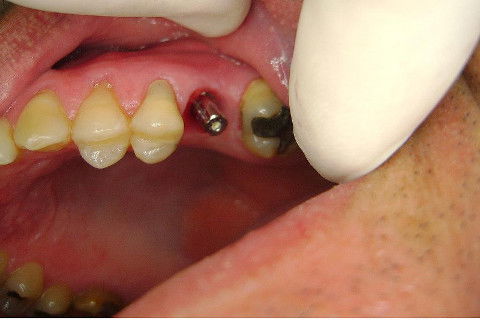

Instalação de um implante em região do 26. Utilizamos um implante cone morse Alvim Neodent 4.3 X 11,5. Foi uma cirurgia muito rápída e minimamente traumática, sem retalho e sutura.

Fotos do caso